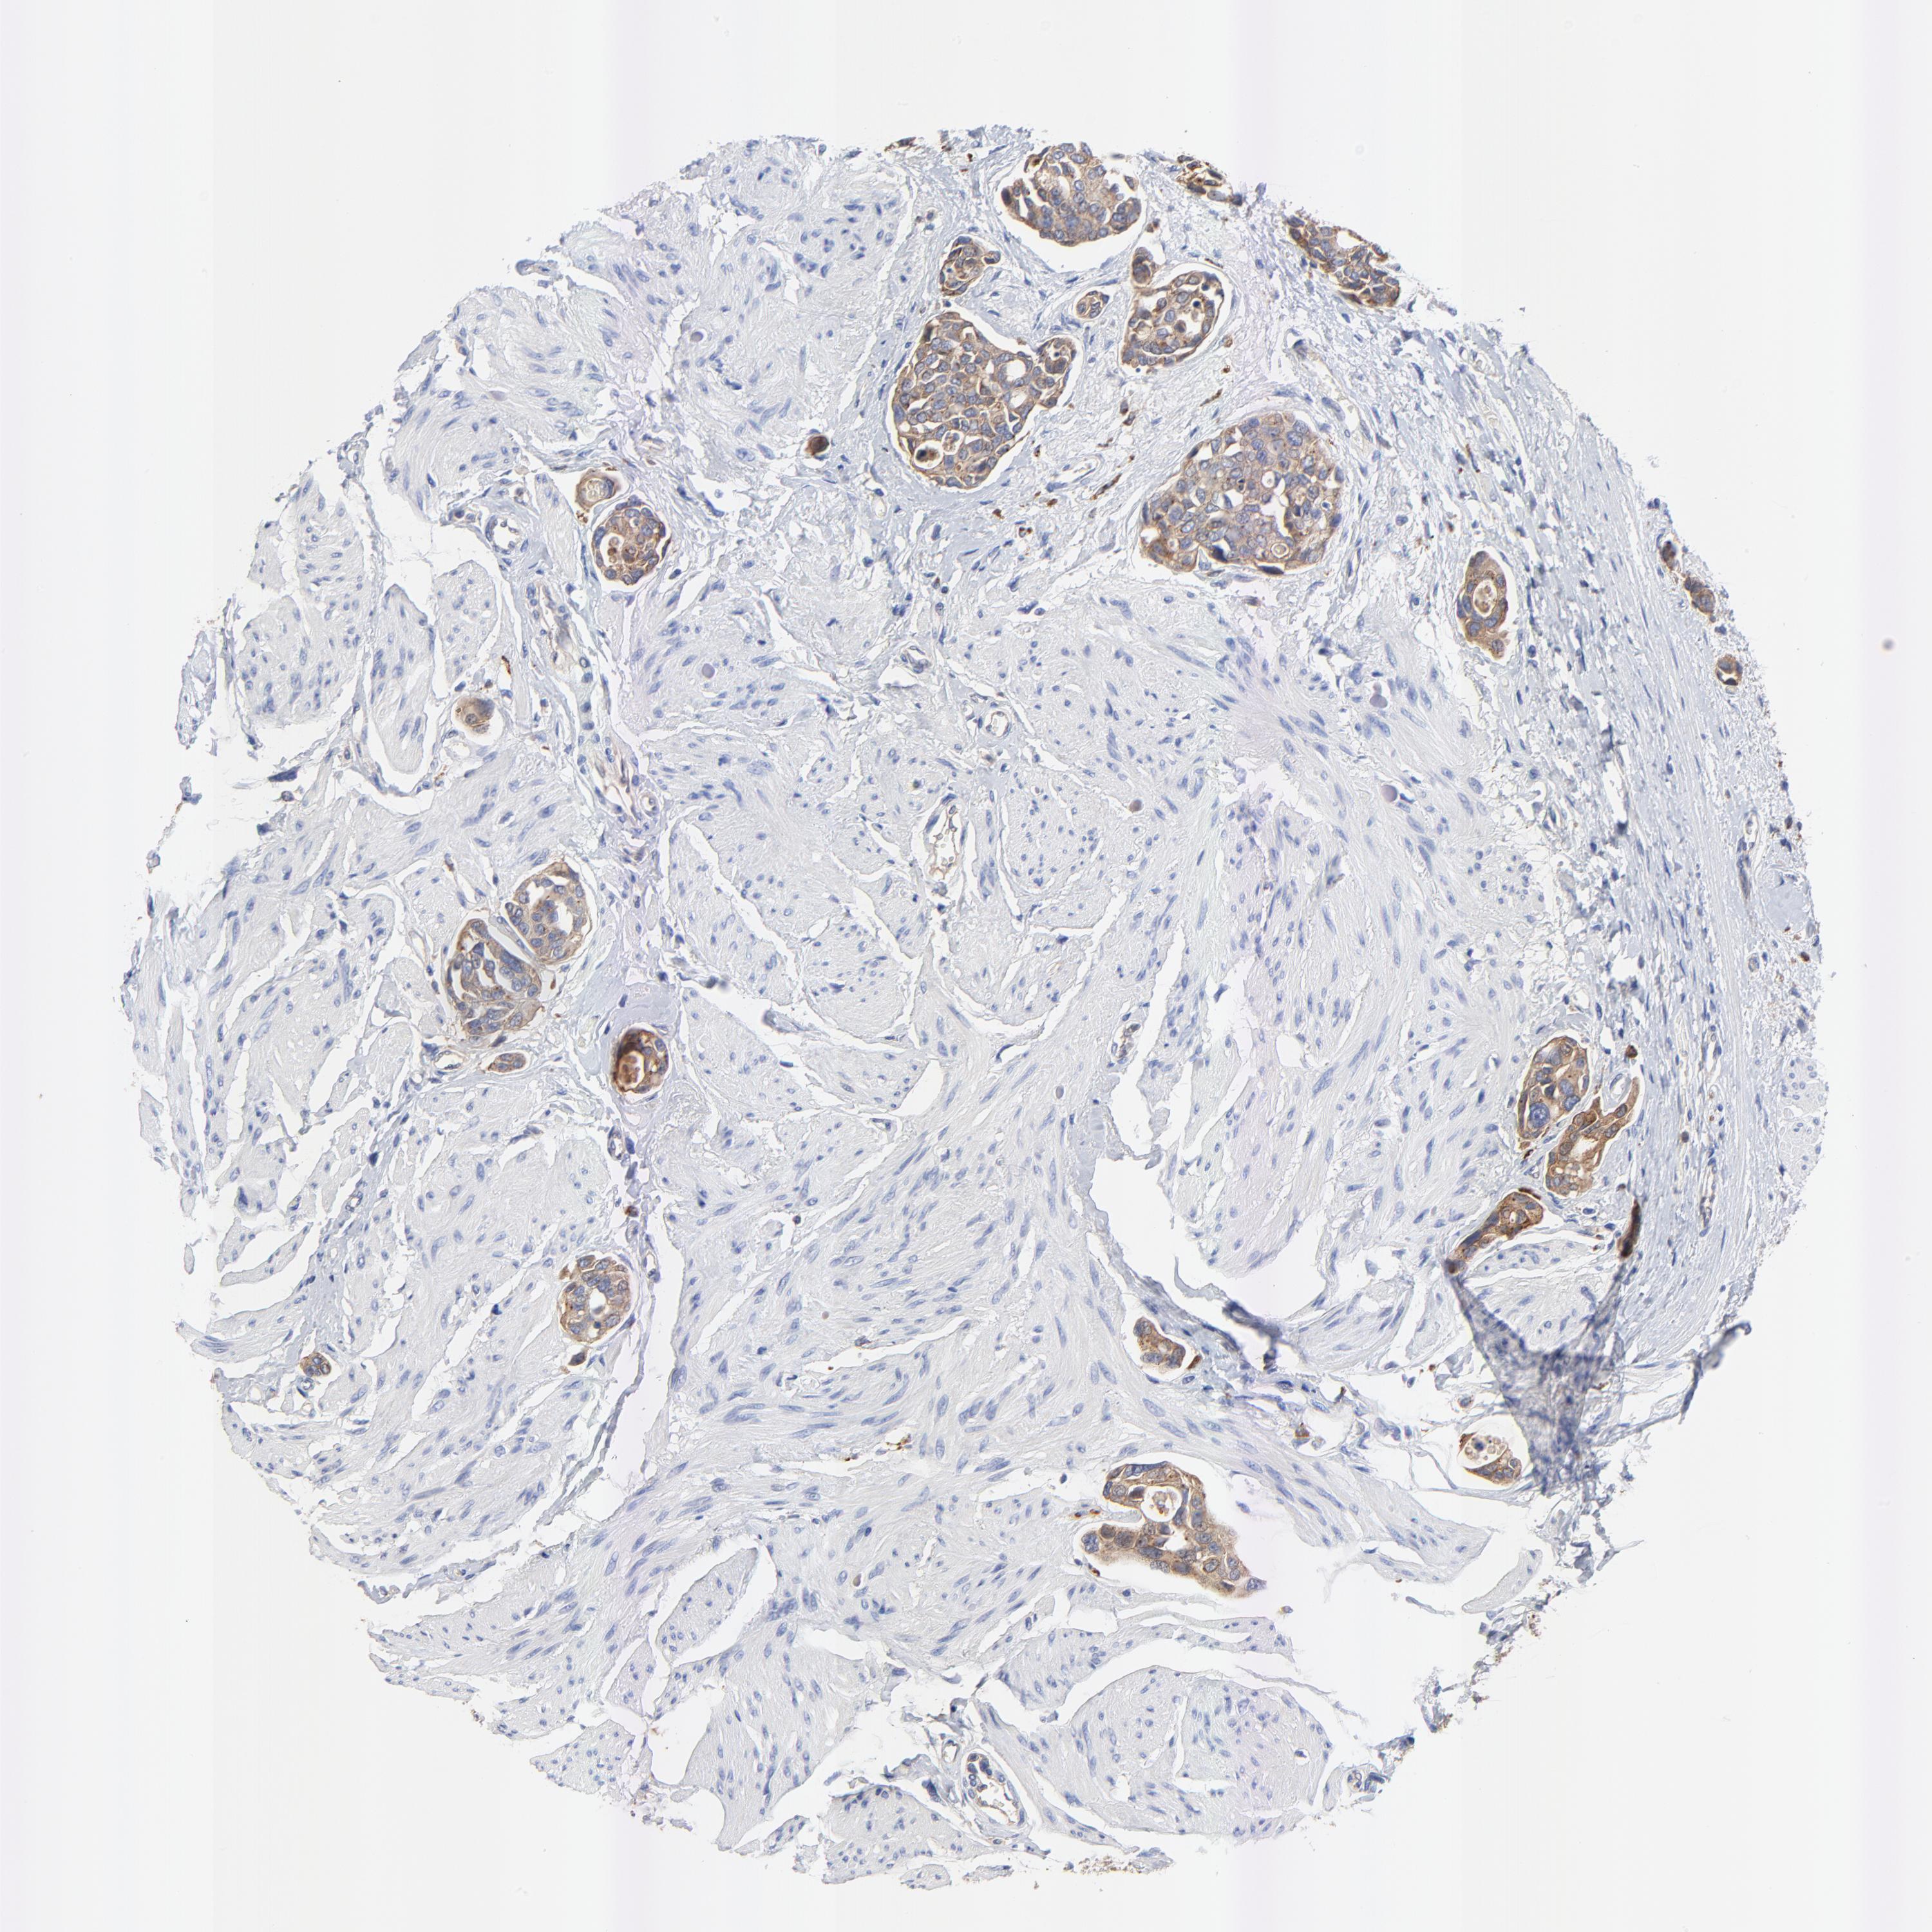

UROTHELIAL CANCER - Protein expressioni

A mouse-over function shows sample information and annotation data. Click on an image to view it in a full screen mode. Samples can be filtered based on level of antibody staining by selecting one or several of the following categories: high, medium, low and not detected. The assay and annotation is described here.

Antibody stainingi

Antibody staining in the annotated cell types in the current human tissue is reported as not detected, low, medium, or high, based on conventional immunohistochemistry profiling in selected tissues. This score is based on the combination of the staining intensity and fraction of stained cells.

Each image is clickable and will lead to virtual microscopy that enables deeper exploration of all samples and also displays staining intensity scores, fraction scores and subcellular localization as well as patient and tissue information for each sample.

Antibody HPA003240

Staining

High

Medium

Low

Not detected

Intensity

Strong

Moderate

Weak

Negative

Quantity

>75%

75%-25%

<25%

None

Location

Nuclear

Cytoplasmic/membranous

Cytoplasmic/membranous,nuclear

Urothelial carcinoma, High grade

Urothelial carcinoma, Low grade